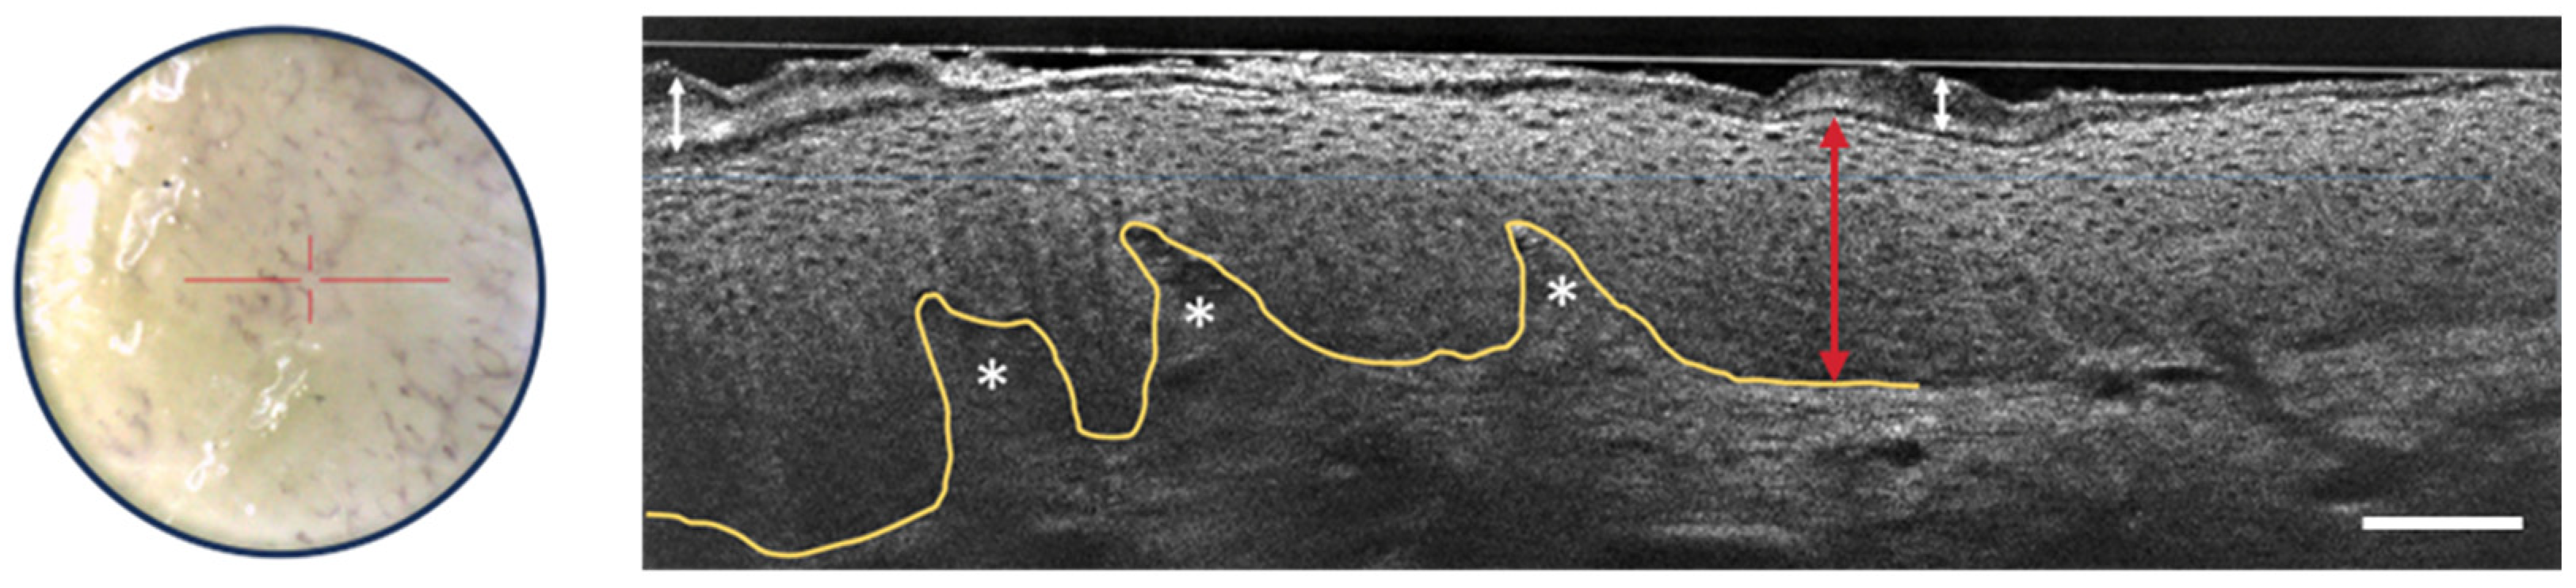

3.1. Melanocytic Skin Tumors

- Schuh, S.; Ruini, C.; Perwein, M.K.E.; Daxenberger, F.; Gust, C.; Sattler, E.C.; Welzel, J. Line-Field Confocal Optical Coherence Tomography: A New Tool for the Differentiation between Nevi and Melanomas? Cancers 2022, 14, 1140. [Google Scholar] [CrossRef] [PubMed]

- Perez-Anker, J.; Puig, S.; Alos, L.; García, A.; Alejo, B.; Cinotti, E.; Cano, C.O.; Tognetti, L.; Lenoir, C.; Monnier, J.; et al. Morphological evaluation of melanocytic lesions with three-dimensional line-field confocal optical coherence tomography: Correlation with histopathology and reflectance confocal microscopy. A pilot study. Clin. Exp. Dermatol. 2022, 47, 2222–2233. [Google Scholar] [CrossRef]

- Lenoir, C.; Perez-Anker, J.; Diet, G.; Tognetti, L.; Cinotti, E.; Trépant, A.; Rubegni, P.; Puig, S.; Perrot, J.; Malvehy, J.; et al. Line-field confocal optical coherence tomography of benign dermal melanocytic proliferations: A case series. J. Eur. Acad. Dermatol. Venereol. 2021, 35, E399–E401. [Google Scholar] [CrossRef]